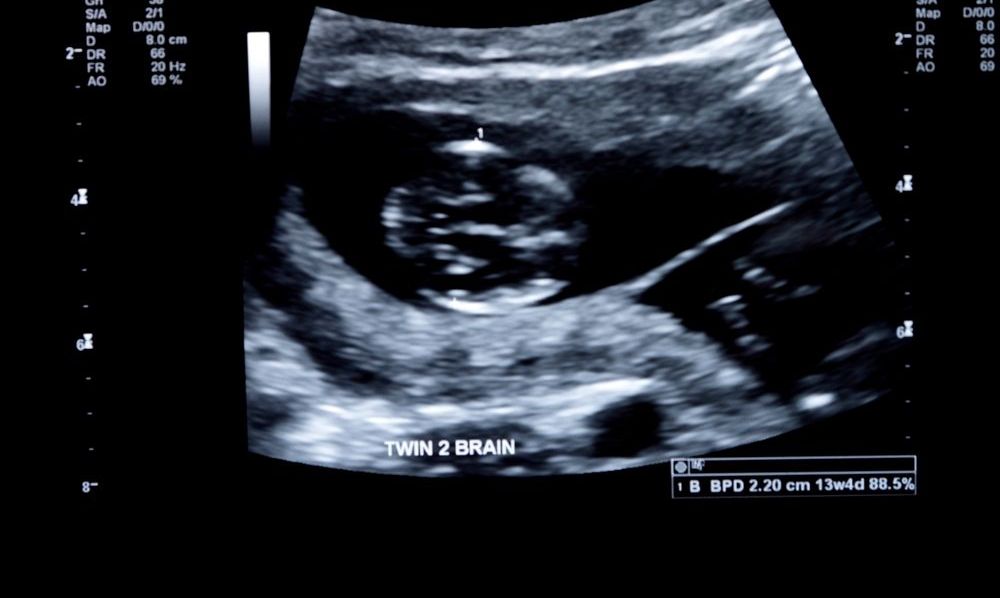

En primera instancia, los médicos pensaron que se trataba de un tumor, pero al realizar la tomografía computarizada, notaron que el bulto tenía cabello, dientes, costillas, hueso largos y vértebras: se trataba de un gemelo que no se desarrolló durante el embarazo y que fue encapsulado por la joven durante la gestación.

Al extirparlo, los doctores confirmaron sus sospechas: el feto medía 36x16x10 centímetros y es el caso más grande de feto in fetu reportado hasta ahora.

Un feto que sobrevive de esta manera no logra desarrollar su propio sistema nervioso ni su cerebro, pero se mantiene vivo a través de su hermano, por lo que en términos llanos se convierte en un parásito.